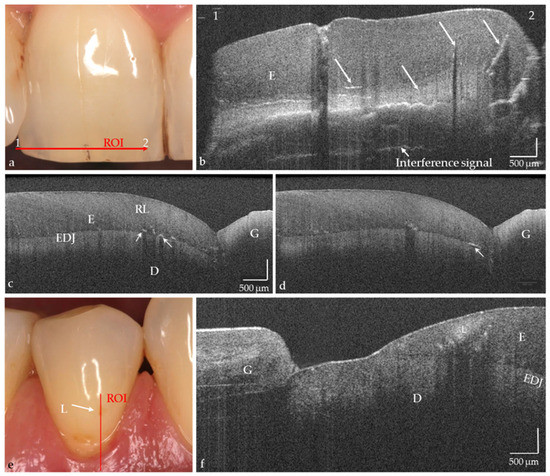

The hard tooth tissues enamel, dentin, and cement, including intrinsic structures such as Retzius lines or defects, could be imaged both on the phantom head and intraorally (Figure 4a–d, in vivo). The cross-sectional OCT images were comparable to those obtained with the laboratory probe. Early carious lesions and their dimensions were displayed in vitro and in vivo, whereby discolorations and demineralized zones could also be distinguished (Figure 4e,f). Micro-cavitations in the enamel could be verified in vitro (Figure 5).

In vivo imaging of hard tooth tissues (a–f), intrinsic structures, and defects in enamel ((b–d), arrows). Partially also Retzius lines (RL; (c)) and superficial tissue structures of the gingiva (f) are indicated. (e) Premolar with vestibular brown discoloration. The OCT cross-sectional image (f) showed that besides the discoloration a carious lesion in enamel (L) is present. The lesion body appears as a bright zone with clear shadowing. Scales are related to refractive index n = 1.0. While the horizontal scale in an OCT cross-sectional image is independent of the refractive index (n) of the tooth structures, the length of the vertical scale has to be divided by it (mean n for enamel and dentin approx. 1.5). Enamel (E), dentin (D), enamel-dentin junction (EDJ), gingiva (G), region of interest (ROI).

On hard tooth tissues, the imaging depth was up to 2.5 mm (Figure 6). The spatial resolution of the probe also partially allowed the visualization of superficial tissue structures of the gingiva (Figure 4e,f). The 90°-optics and the ergonometric design of the probe allowed the dentist to manually image all occlusal, vestibular, oral, and proximal tooth surfaces including those of the second molars and the occlusal, oral and proximal surfaces of the third molars. The vestibular surfaces of third molars and proximal surface areas of the molars within a “blind spot” at a distance greater than 2.5 mm from the tooth surfaces could not be imaged. While a B-scan is recorded in real time, the scan time for a C-scan is approximately 28 seconds.